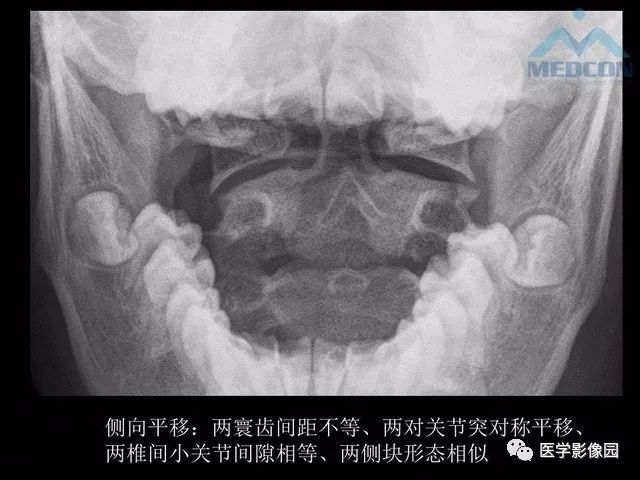

寰枢关节脱位的影像学诊断

寰枢关节半脱位x片

寰枢关节脱位图片

寰枢关节张口位